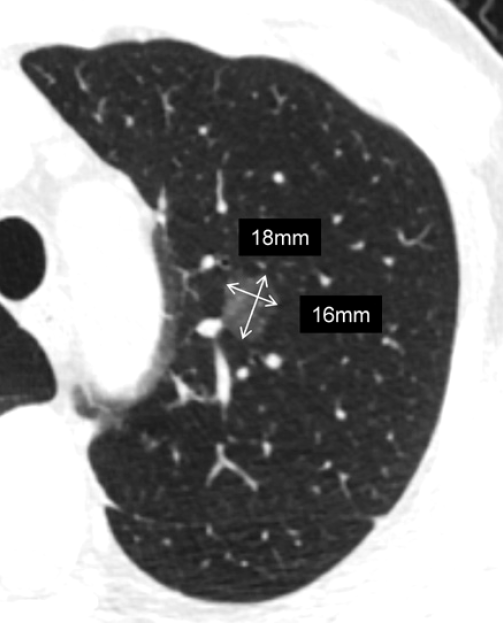

左肺上叶纯磨玻璃结节。前一病例的结节测量方法同样适用于此病例,此结节的平均直径为17mm。